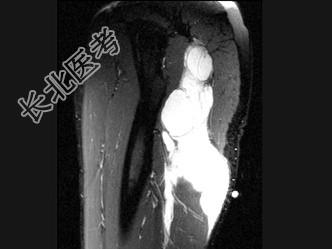

- 单项选择题女,47岁, 足部疼痛,运动员, 结合图像,最可能的诊断是 ( )

A、肌内黏液瘤

B、脂肪瘤

C、血管瘤

D、肌内脓肿

E、滑膜肉瘤